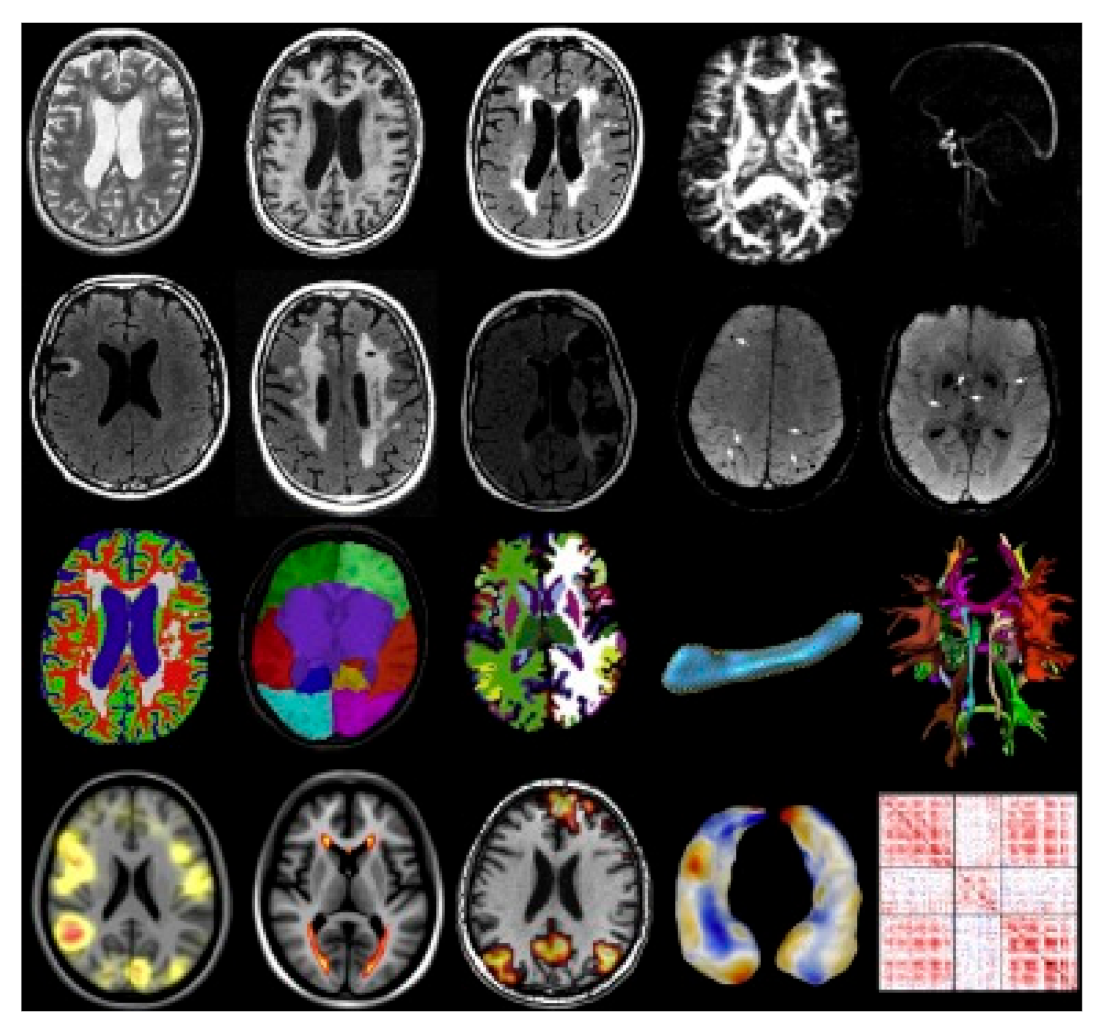

2.3. Neuroimaging